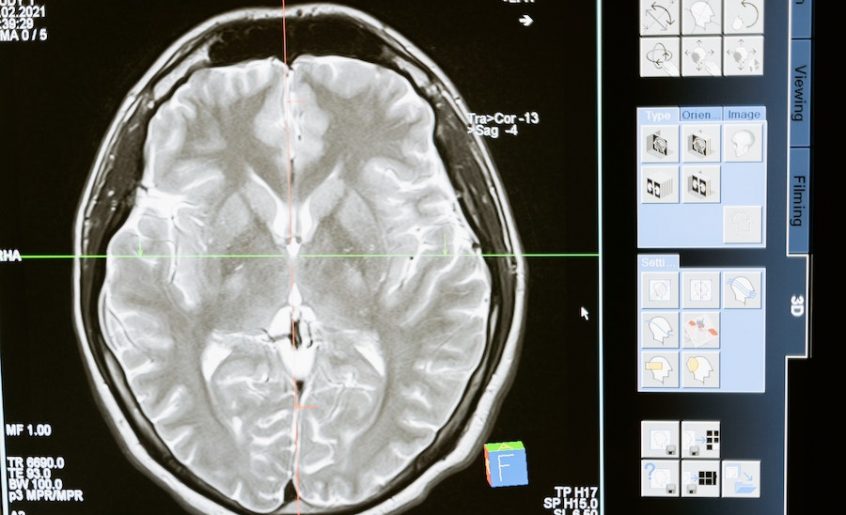

Do nezgode ili moždanog udara dolazi kada je blokiran protok krvi u arterijama koje hrane mozak, ili kada se krvarenje dogodi u samom mozgu ili u membranama koje ga okružuju. Moždani udar se može desiti svakome bilo kad i svako treba da zna znakove upozorenja. U proseku, 1,9 miliona moždanih ćelija umre svake minute kada se moždani udar ne leči. Moždani udar je jako opasan po čoveka i nužno je hitno reagovati odlaskom u najbližu zdravstvenu ustanovu ili pozivom hitne pomoći. Rano lečenje dovodi do veće stope preživljavanja i niže stope invaliditeta.

Moždan udar koji se javlja u zadnjem delu mozga nastaje kada je krvni sud u zadnjem delu mozga blokiran, izazivajući smrt moždanih ćelija (nazvan infarkt) u predelu začepljenog krvnog suda. Ova vrsta moždanog udara može biti uzrokovana i pucanjem krvnog suda u zadnjem delu mozga. Kada se desi ova vrsta moždanog udara, javlja se nekoliko simptoma i oni mogu biti veoma različiti od simptoma koji se javljaju u cirkulaciji krvi u prednjem delu mozga. Ovi simptomi moždanog udara uključuju: vrtoglavicu, neravnotežu ili jednostrana slabost ruku ili nogu, nejasan govor ili teškoće u govoru, dvostruki vid ili drugi problemi sa vidom, glavobolju, mučninu i povraćanje.